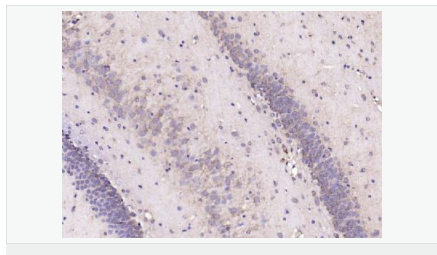

| 產(chǎn)品應(yīng)用 | ELISA=1:5000-10000 IHC-P=1:100-500 IHC-F=1:100-500 IF=1:200-800 (石蠟切片需做抗原修復(fù)) not yet tested in other applications. optimal dilutions/concentrations should be determined by the end user. |

| 產(chǎn)品介紹 | This gene encodes a member of the corticotropin-releasing factor family. The encoded preproprotein is proteolytically processed to generate the mature neuropeptide hormone. In response to stress, this hormone is secreted by the paraventricular nucleus (PVN) of the hypothalamus, binds to corticotropin releasing hormone receptors and stimulates the release of adrenocorticotropic hormone from the pituitary gland. Marked reduction in this protein has been observed in association with Alzheimer's disease. Autosomal recessive hypothalamic corticotropin deficiency has multiple and potentially fatal metabolic consequences including hypoglycemia and hepatitis. In addition to production in the hypothalamus, this protein is also synthesized in peripheral tissues, such as T lymphocytes, and is highly expressed in the placenta. In the placenta it is a marker that determines the length of gestation and the timing of parturition and delivery. A rapid increase in circulating levels of the hormone occurs at the onset of parturition, suggesting that, in addition to its metabolic functions, this protein may act as a trigger for parturition. [provided by RefSeq, Nov 2015] Function: This hormone from hypothalamus regulates the release of corticotropin from pituitary gland. Subunit: Interacts (via C-terminus) with CRFR1 (via N-terminal extracellular domain). Subcellular Location: Secreted. Similarity: Belongs to the sauvagine/corticotropin-releasing factor/urotensin I family. SWISS: P06850 Gene ID: 1392 Database links: Entrez Gene: 1392 Human Entrez Gene: 12918 Mouse Omim: 122560 Human SwissProt: P06850 Human SwissProt: Q8CIT0 Mouse Unigene: 75294 Human Unigene: 290689 Mouse Unigene: 10349 Rat Important Note: This product as supplied is intended for research use only, not for use in human, therapeutic or diagnostic applications. CRF陽性神經(jīng)元的胞體廣泛分布于下丘腦的室旁核、背縫核和藍斑核,這些區(qū)域也是去甲腎上腺素(NE)神經(jīng)元與5-羥色胺(5-HT)神經(jīng)元密集的區(qū)域。 CRF既具有神經(jīng)遞質(zhì)的性質(zhì)又具有神經(jīng)激素的性質(zhì)。CRF是聯(lián)系神經(jīng)系統(tǒng)與內(nèi)分泌系統(tǒng)的橋梁,在情感障礙疾患如焦慮和抑郁的發(fā)病中發(fā)揮重要作用. |